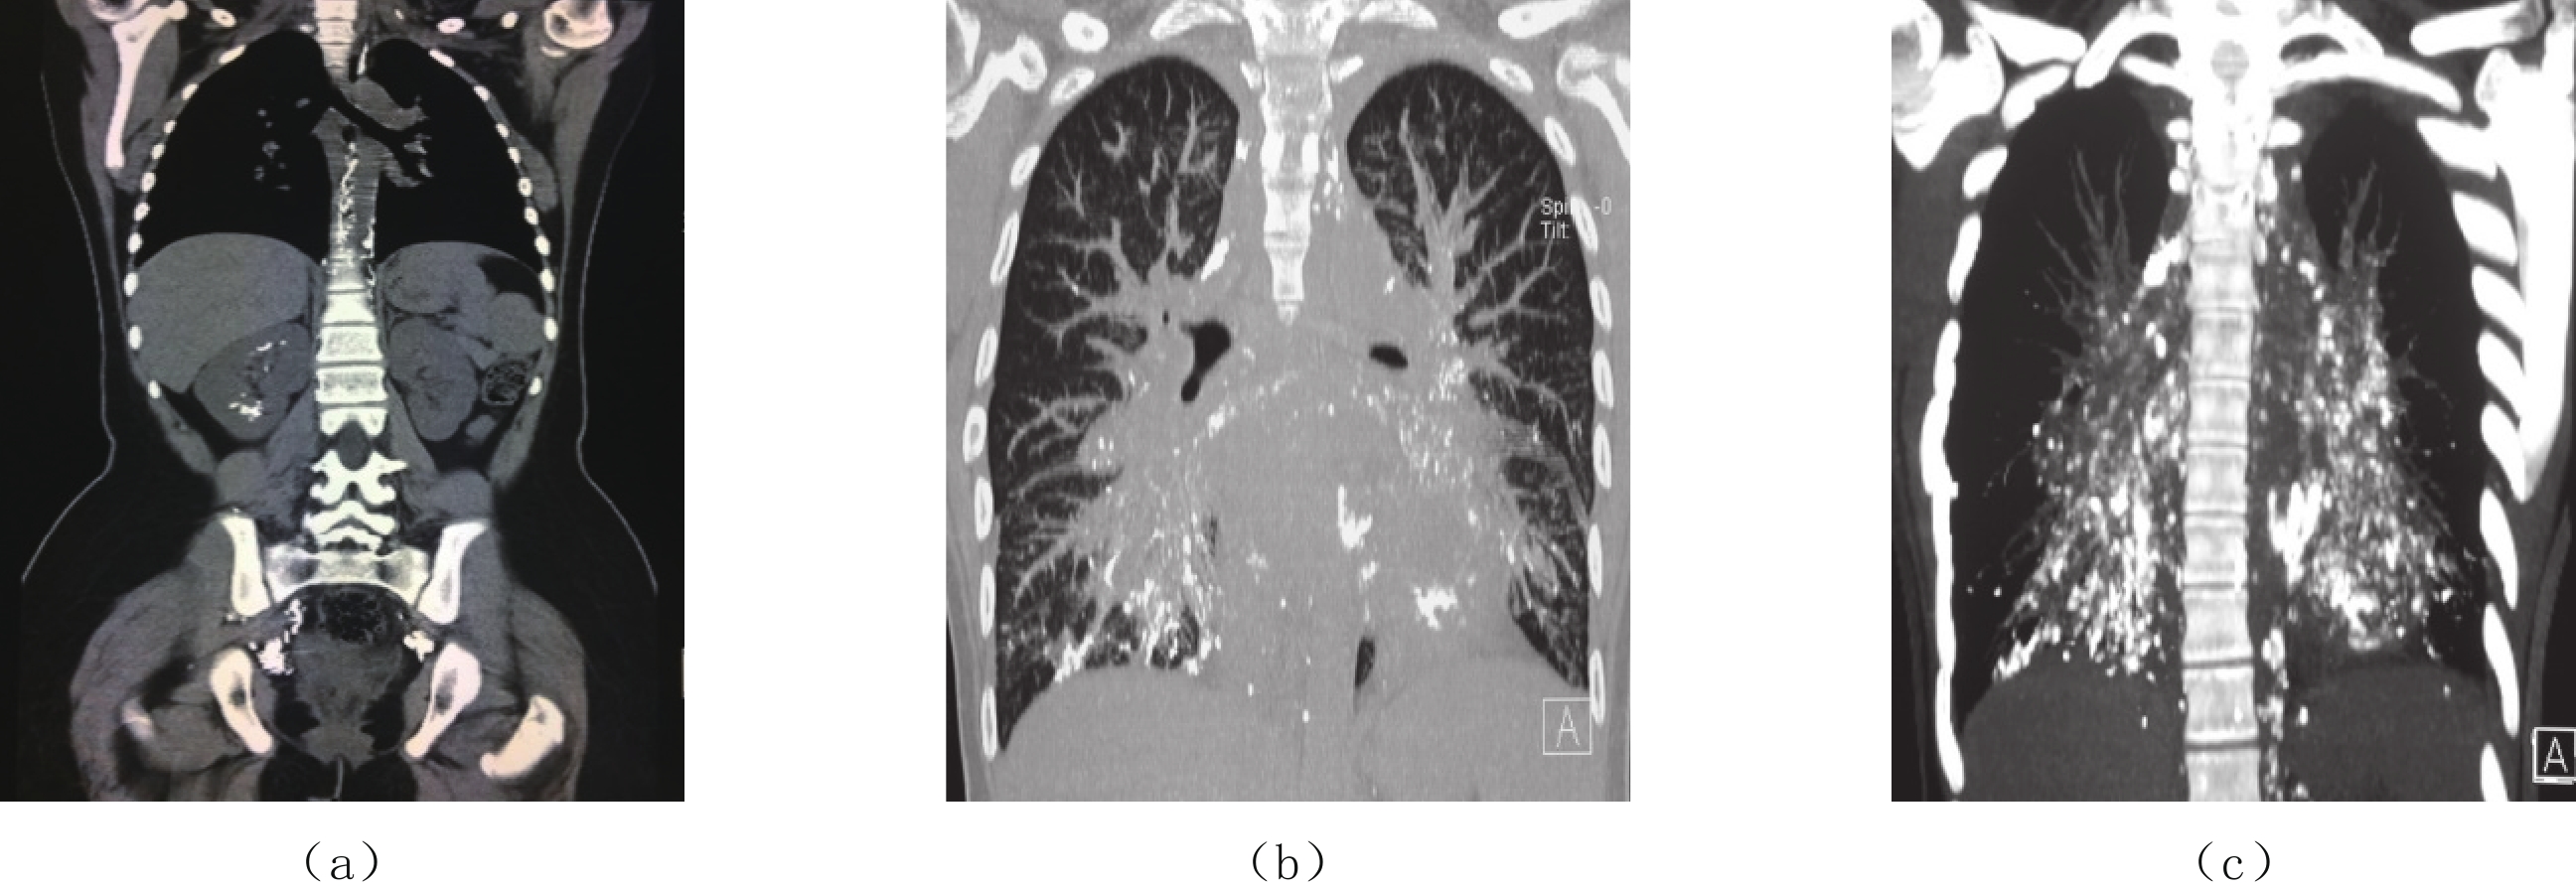

CTL以平扫和三维重建方式进行成像,可准确显示对比剂在不同区域淋巴管内外的分布、各种淋巴管异常和淋巴回流及乳糜漏出的部位和范围,而且还可显示淋巴结内的对比剂的聚集,对淋巴结的形态和功能做出更为准确的诊断。

结合DLG可直观动态显示淋巴液的流动方向、乳糜漏出的部位、胸导管的形态及术后淋巴引流的异常等,CTL对于判断有无淋巴回流障碍、乳糜返流和漏出、病变部位和范围、分期和分级、明确治疗方案、疗效评估和动态演变、风险因素预警等具有重要意义[11-15]。

CTL检查可以明确:①淋巴水肿的部位、范围和返流程度,即精准定量诊断、分期和分级评价;②水肿的类型,单纯水肿不伴淋巴管畸形、淋巴水肿伴淋巴漏出或乳糜池形成、淋巴水肿伴明确的淋巴管畸形或血管畸形等;③全身其他部位有无异常或淋巴管道畸形等,尤其集合淋巴管和胸导管有无梗阻、扩张、畸形以及瓣膜结构和形态的改变;④淋巴水肿的进展规律和动态演变;⑤治疗前后淋巴管的修复和疗效评估等。

CTL检查可以明确:①乳糜漏的具体部位、范围和程度;②乳糜漏是否伴有局部或全身淋巴水肿或淋巴管畸形;③指导临床明确治疗方法和手术路径;④治疗前后的疗效评估等。

CTL检查可以明确:①淋巴管畸形的部位和范围;②淋巴管畸形的CT类型,局限型(单囊和多囊)、多发性囊性淋巴畸形和弥漫性淋巴管畸形,其中弥漫型又分为肿胀型、管道型和混合型;③是否伴有局部或全身淋巴水肿或乳糜漏及其他异常;④指导临床明确治疗方法和手术路径;⑤治疗前后的疗效评估等。